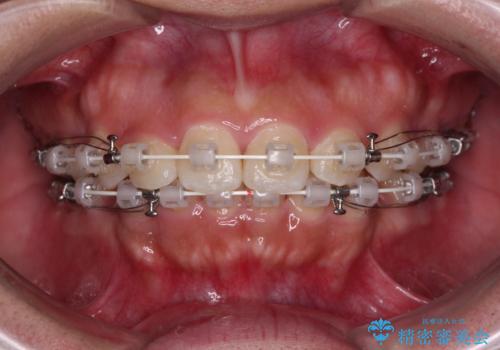

デコボコと口元の突出感が認められたため、上下左右の第1小臼歯4本を抜歯してのワイヤー矯正を行うこととしました。

上顎歯列の横幅が狭く、下顎大臼歯の歯軸が舌側に倒れていたため、急速拡大装置により上顎骨を側方に拡大し、咬み合わせを改善することとしました。

上顎歯列幅を拡大したことで、デコボコを容易に解消することができるようになったため、抜歯により得られたスペースを口元の突出感改善に利用することができました。